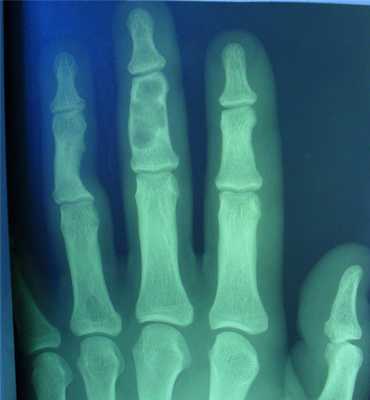

- поражаются фаланги, пястные, плюсневые, реже запястные кости, отростки позвонков, передние концы верхних ребер, тазовый скелет, грудина и весьма редко - длинные трубчатые периферические кости,

- в малых цилиндрических костях хондромы гнездятся в диафизах и эпифизах, в больших трубчатых - только в метафизарных костях,

- как правило хрящевые опухоли множественны и чаще всего наблюдаются в числе одного или нескольких на фалангах рук и пястных костях,

- чаще процесс двусторонний, но не симметричный.

- опухоли шарообразны или овальны, расположены то центрально и вздувают кость изнутри, то эксцентрично и более поверхностно и связаны только с корковым веществом кости,

- опухоль состоит из прозрачного, хрящевого фона на котором видны островки, точечки из извести или костного вещества,

- наружные контуры гладкие и при доброкачественном течении не прерываются,

- на месте слияния опухолевых шаров костная перегородка иногда толстая, в других случаях истончена или отсутствует,

- при поражении эпифизарных хрящей приходится видеть торможение роста кости в длину или ее искривлении,

- нередко центрально расположенная хондрома осложняется патологическим переломом,

- корковый слой неравномерен и местами утолщен,

- при хондроме поверхность кости шероховата.